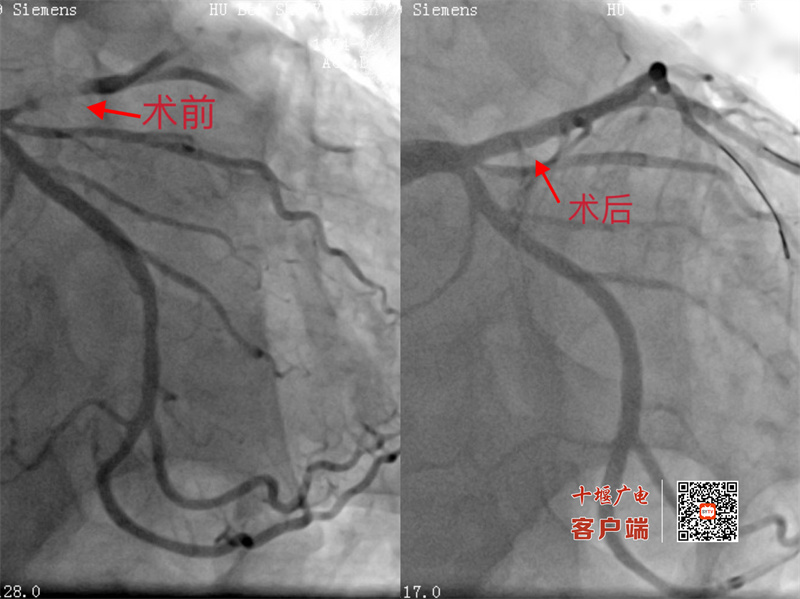

在生命支持系统的保障下,心内科2病区吴三五主任带领介入团队争分夺秒为患者施行冠脉造影。造影发现心脏前降支近段血管完全闭塞,情况万分危急。吴三五主任及其团队沉着应对,成功于病变血管植入一枚支架,打通了堵塞的“生命要道”。从入院到血管再通,整个过程不到两小时,每一步都精准高效。